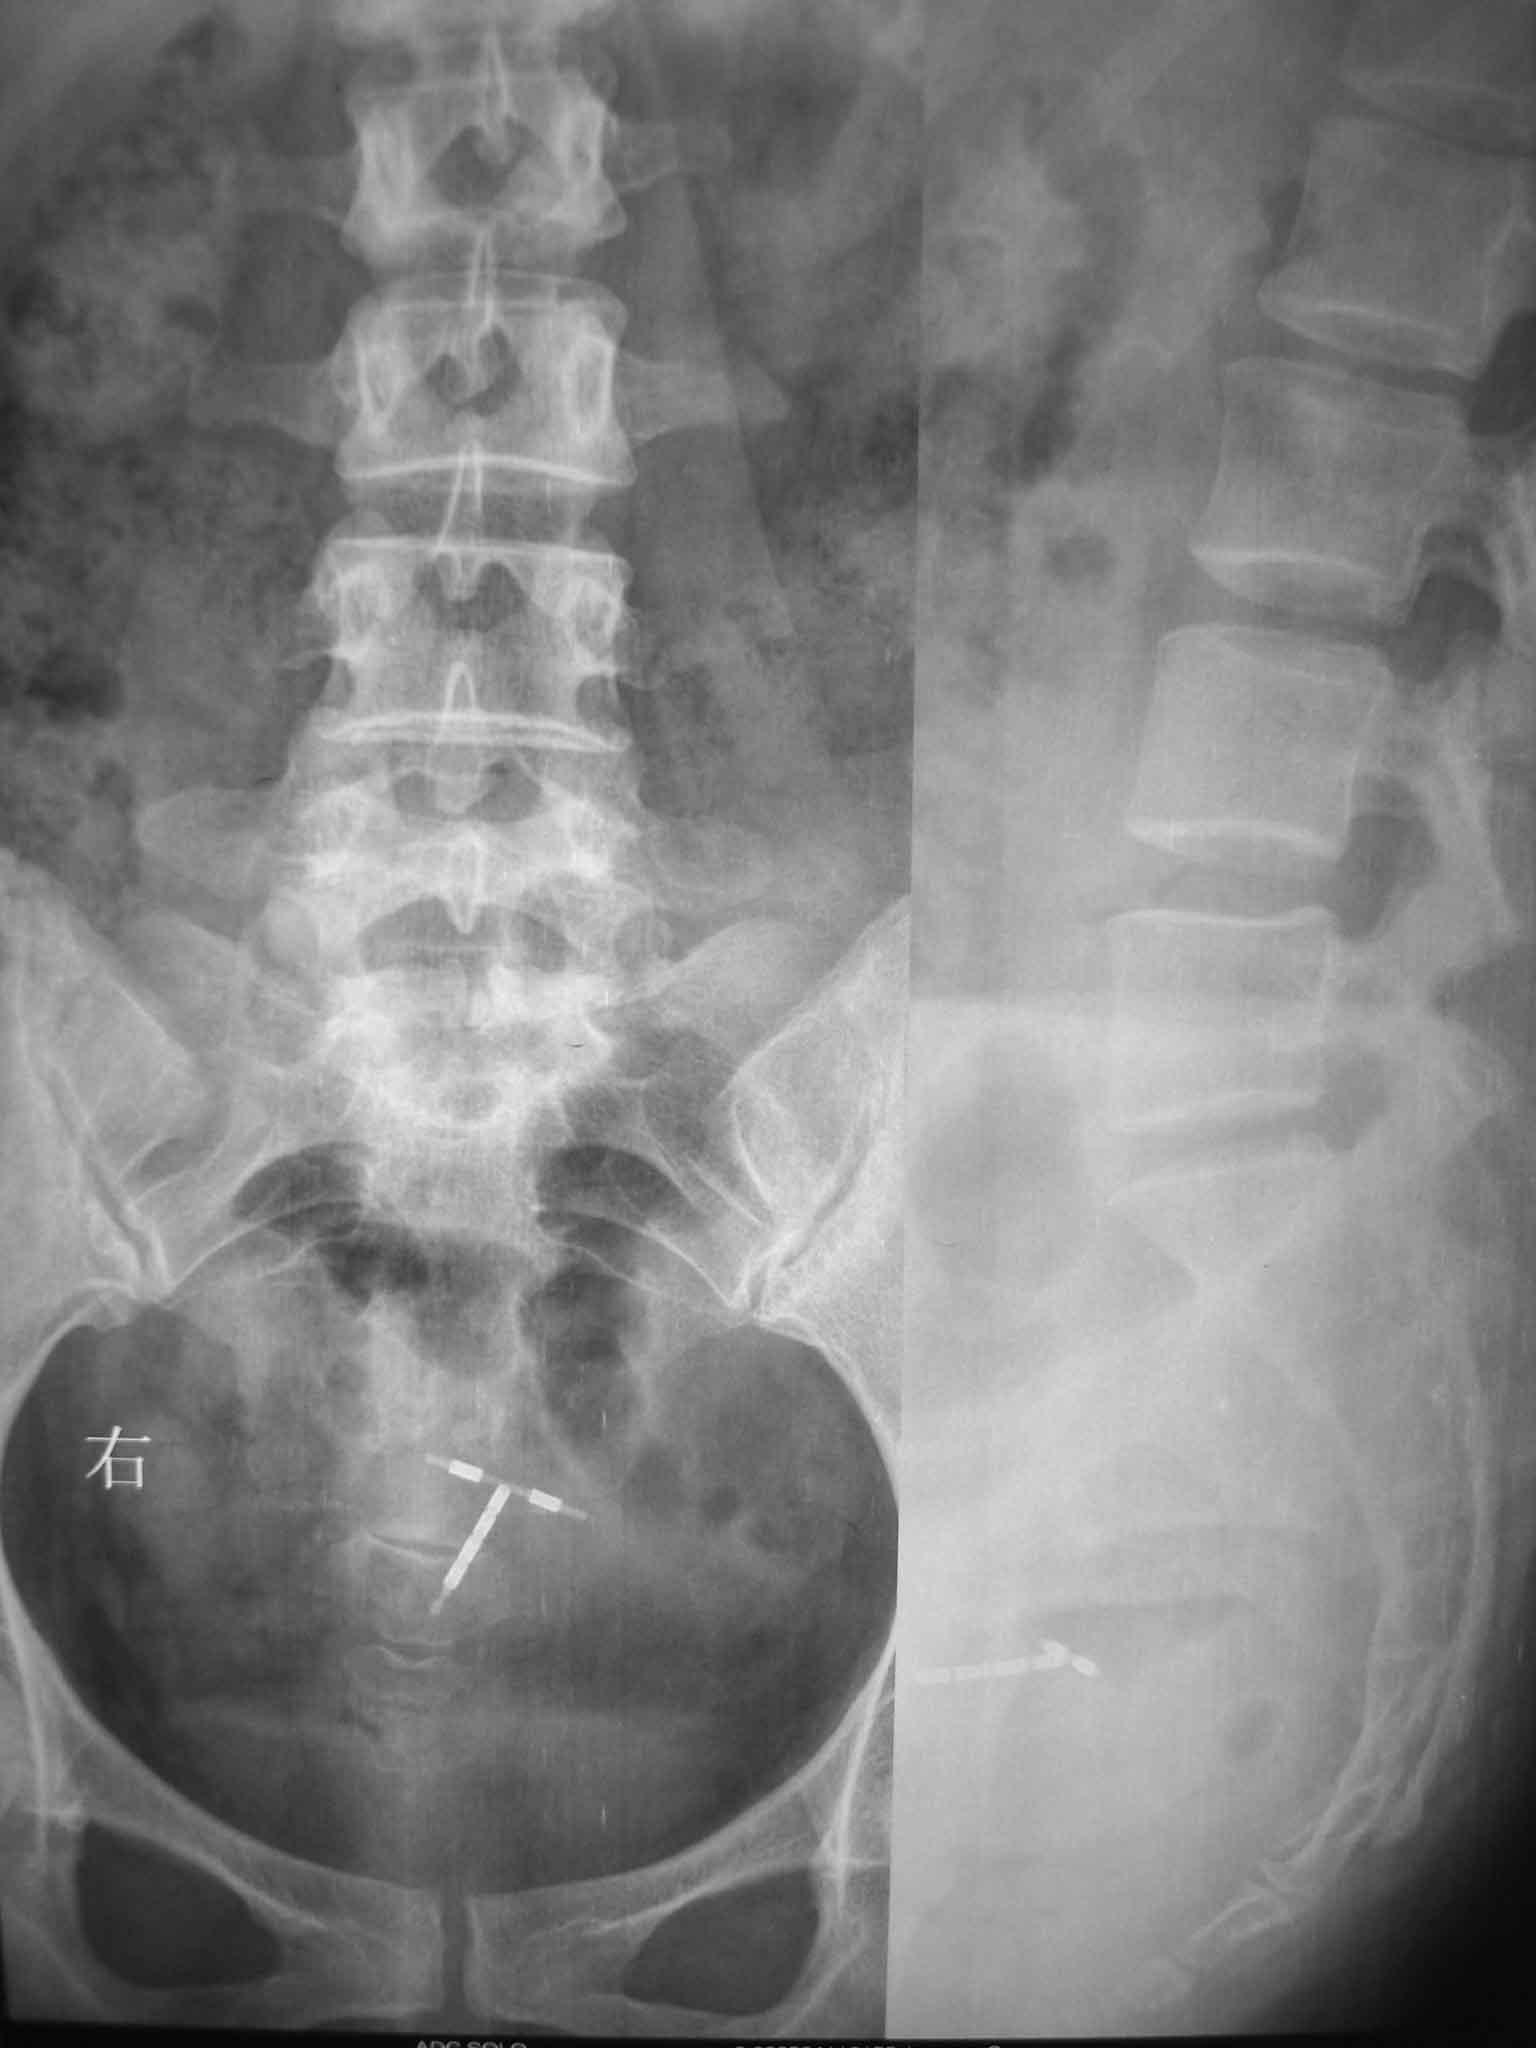

标题: CT15385:F48Y,腰疼一周拍片。

女性,48岁,腰疼一周右腿麻木。不敢弯腰,弯腰疼痛放散至右国窝。

两侧的腰大肌影不对称,不知为何?

隐性骶椎裂并游离棘突。